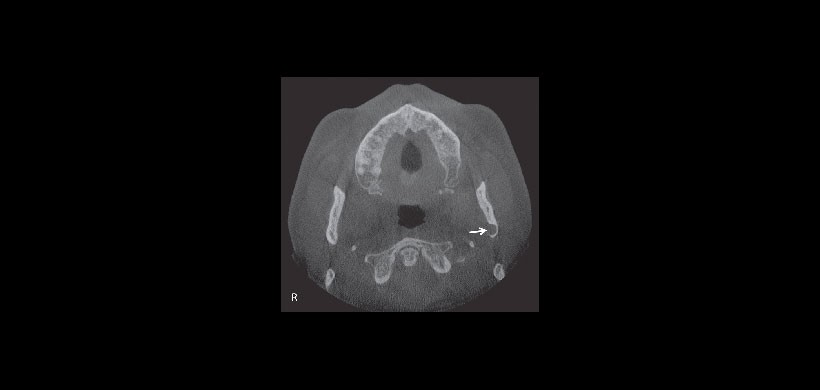

Fig 4. Tomografía computarizada de haz cónico. Vista axial muestra la depresión a nivel de la rama mandibular izquierda